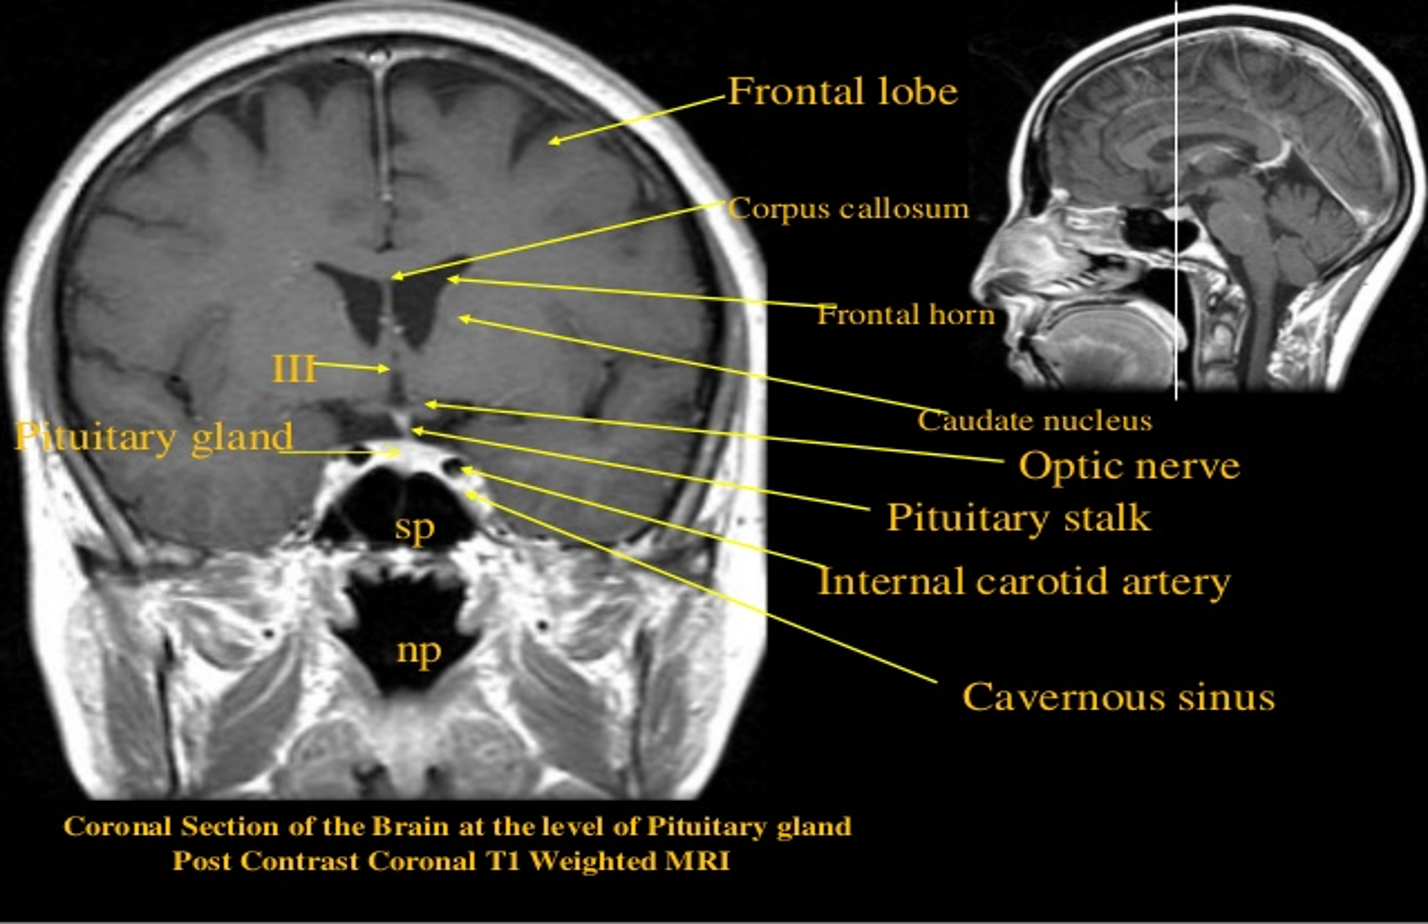

Intracranial enhancement on computed tomography and magnetic resonance imaging

Physiological

- Choroid

- Anterior pituitary gland

- Arteries

- Dural venous sinuses

Coronal